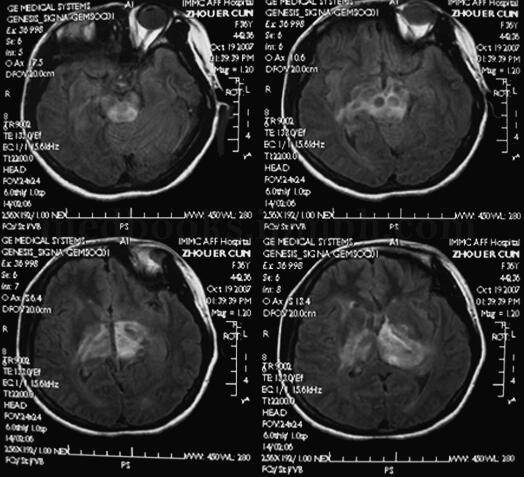

入院查体:强迫体位,神志清楚,躁动不安,呼吸急促。满月脸,贫血貌。四肢末梢、大腿内侧皮肤花斑,颈部胸前有10cm×10cm瘀斑。构音障碍,右侧鼻唇沟浅,软腭抬举度差,咽反射(+)。左侧肢体肌力4级,右侧肢体肌力3级,双手摸索、强握动作,双侧腹壁反射(+),双侧肱二头、三头肌腱、膝腱及跟腱反射对称(+++),双侧Hoffmann征(+),双侧Babinski征(-),Chaddock征(+)。颈软无抵抗,Kernig征(-)。2008年3月26日头颅MRI(图2.1‐1)左侧中脑、脑桥、丘脑弥漫性肿胀、脱髓鞘改变。

图2﹒1‐1 头颅MRI 左侧中脑、脑桥、丘脑弥漫性肿胀、脱髓鞘改变

本病无特征性临床表现,病程较短且进展较快,临床症状常与肿瘤所在的位置有关,主要症状有头痛、呕吐、视乳头水肿和偏瘫,感觉减退,少数患者可有癫痫、精神障碍等。本例患者为青年女性,病程6个月,症状逐渐进展,主要表现为认知功能减退,不自主动作,中枢性过度换气,查体有构音障碍,左侧鼻唇沟变浅,双侧软腭抬举差,咽反射减退,双侧锥体束征阳性。头颅MRI见:沿大脑中线两侧白质为主到脑干、第四脑室周围T1等信号、T2长信号影,结构饱满感。临床表现和体征与多病灶基本符合。